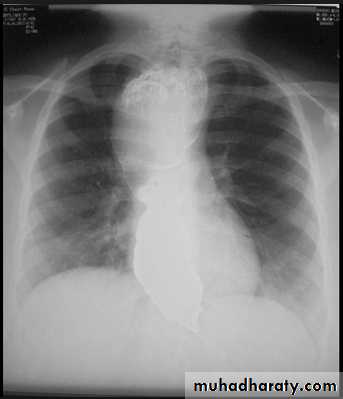

Hodgkin Lymphoma. A. Posteroanterior chest radiograph in a 35-year-old man shows a large, lobulated mediastinal mass. B. Contrast-enhanced CT at the level of the aortic arch shows bulky anterior and middle mediastinal lymphadenopathy